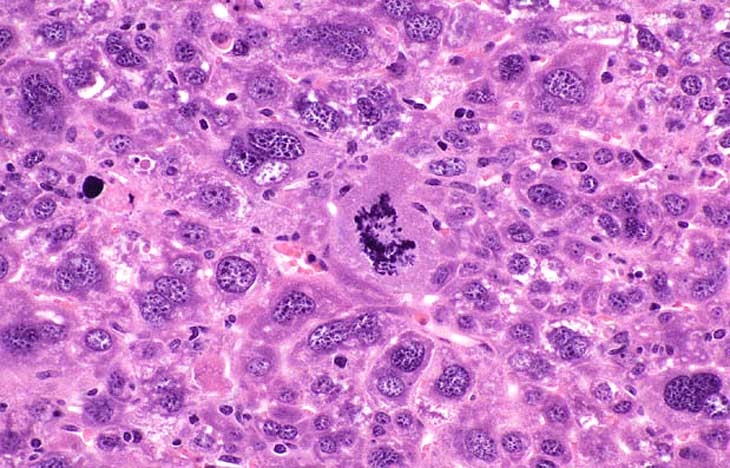

Higher magnification of liver lesions in a 4-week old AL-TAg x AL-myc mouse.

Higher magnification of a well differentiated cholangiocarcinoma in a 4-week old AL-TAg x AL-myc mouse.

A hepatocellular carcinoma in a 4-week old AL-TAg x AL-myc mouse.

Hepatocytomegaly, karyomegaly, and a mitotic figure in a 39- day-old transgenic mouse.

Anaplastic cytology is present in this hepatocellular carcinoma in a transgenic mouse.